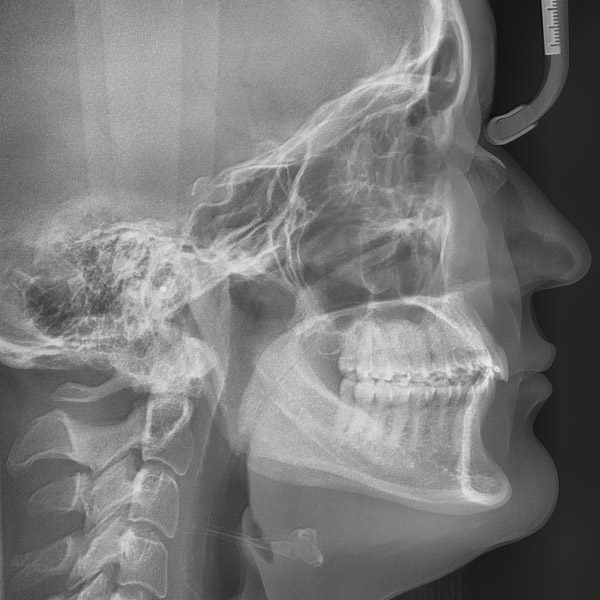

Für die genaue Planung der kieferorthopädischen Behandlung mit der Verankerung von Zähnen, zur Entscheidung über die Notwendigkeit zur Zahnentfernung sowie zur Prognose des vorhandenen Wachstums ist das Erstellen von

- Abformung zur Erstellung von dreidimensionalen Gipsmodellen

- Digitale Fotos vom Gesicht und den Zähnen

- Digitale Röntgenbilder von Zähnen und Kiefer erforderlich

Dabei setzen wir sowohl auf klassische und bewährte Methoden als auch moderne digitale diagnostische Verfahren ein.